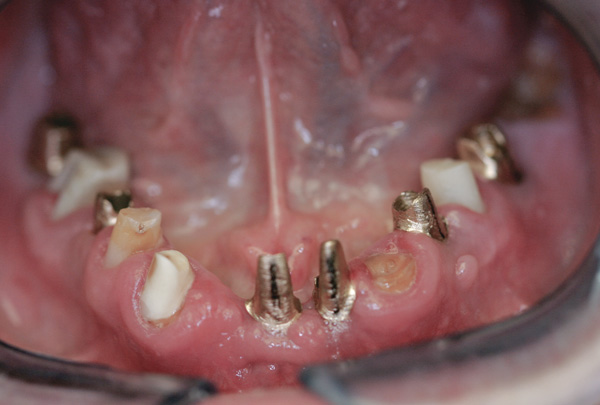

Case 3 – Remilling of Custom Abutments

Background: In this case, the patient had a failing mandibular and maxillary dentition due to caries secondary to radiation-induced xerostomia. The patient had had a radical neck dissection to remove a squamous cell carcinoma of the throat 9 years prior to his prosthodontic consultation with the authors. The patient reported a history of radiation therapy following surgery, but did not have a shielding stent. A staged approach was used so as to avoid removable prosthetics on his severely dry soft tissues. He chose to treat his mandibular issues first. Figure 9 shows healing abutments next to the temporarily retained natural teeth, and Figure 10 shows the first-stage custom abutments inserted with relatively good gingival contour and no recession. Recession was clearly seen around all first-stage abutments following adjacent extractions and second-stage implant placement (Figure 11).

Figure 9 Healing abutments.

Figure 9

Figure 10  First-stage custom abutments.

Figure 10

Figure 11 Recession evident around first-stage abutments following adjacent extractions and second-stage implant placement.

Figure 11